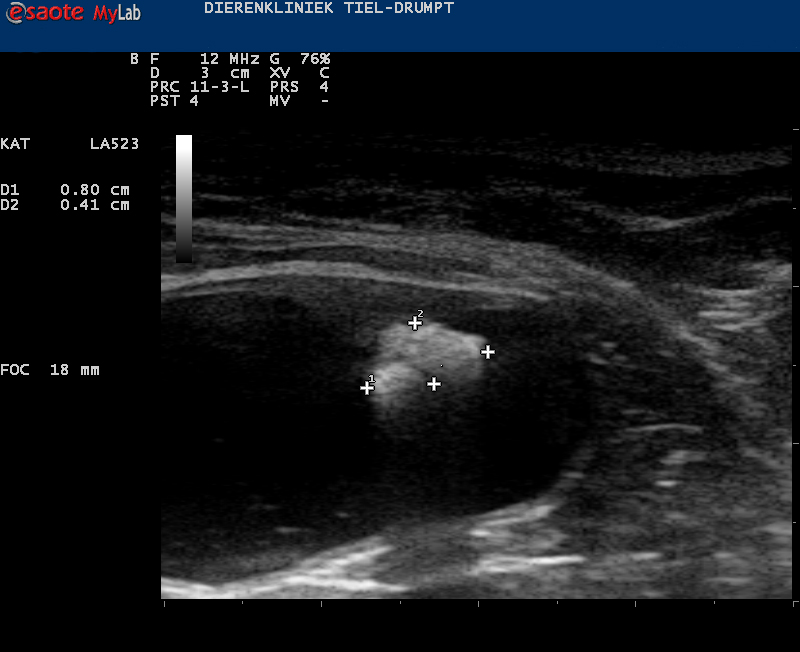

Zo kan er sprake zijn van zwelling of een gezwel bij de penis of een verstopping in de plasbuis door bijvoorbeeld samengeklonterd gruis, een blaassteentje of een plug (dit wordt gevormd door eiwitten, cellen, etc) die een verstopping kunnen geven.Ook structuren in de blaas kunnen de uitmonding verstoppen, zoals steentjes, poliepen, gezwellen, etc.

De prognose van de behandeling bij een verstopping van de penis, zoals bij de plaskater, hangt sterk af van hoe snel er ingegrepen kan worden, de oorzaak van de verstopping en de wijze van behandelen.Er kan bijvoorbeeld gruis aanwezig zijn wat zeer goed te bestrijden is met een medisch dieet. Er bestaat echter ook blaasgruis dat niet goed met een dieet te behandelen is. Als blaasgruis langer onbehandeld aanwezig is, dan kan dit samenklonteren tot stenen.

Deze zullen operatief verwijderd moeten worden want anders blijft er aanleiding tot ontstekingen van de blaas en mogelijk nieuwe verstoppingen. Ook de mate van zwelling in de plasbuis kan zorgen voor risico’s van recidief. Indien de oorzaak een tumor is dan wordt de prognose vaak slechter. Dit hangt echter ook af van de locatie van de tumor.